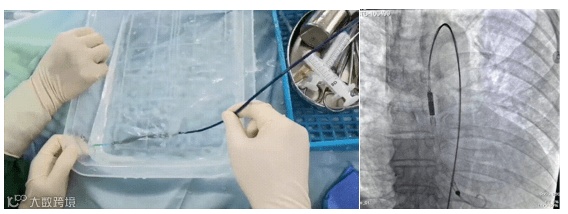

经分析,患者需行冠脉血运重建治疗,但患者病情复杂,手术风险极高。杨人强主任立即组织病例讨论,考虑患者外科手术风险极高,建议行PCI术。但患者心功能差、病变复杂、手术难度大,术中出现血流动力学异常风险高,为有效维持术中血流动力学稳定,拟在机械循环辅助装置支持下行PCI术。经充分跟患者家属沟通后,治疗团队于PCI术前经患者右侧股动脉预先送入 SynFlow3.0 提供心室辅助。

术中,SynFlow3.0 将患者左心室内的血液通过血流通道泵入主动脉中,实现对左心室的辅助泵血,增加了循环支持,保证了全身重要器官的循环灌注,术中患者心率、血压、血氧饱和度等各项生命体征平稳,整个手术持续 3 小时,最终成功实现冠脉完全血运重建。患者术后恢复良好,已康复出院。